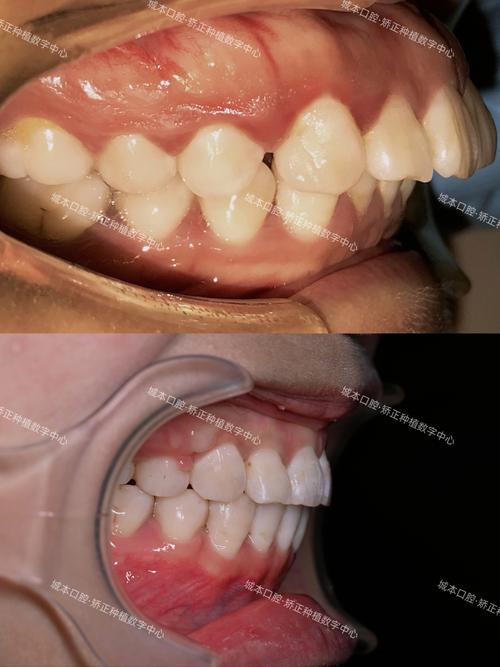

正畸尖牙牙根凸出是指在正畸治疗过程中,由于先天因素或后天干预影响,导致尖牙牙根在牙槽骨内的位置发生异常偏移,表现为牙根唇侧或腭侧超出正常解剖范围,牙槽骨壁可能变薄甚至穿孔,其成因可分为先天性与后天性两大类:

- 视诊与触诊:观察尖牙牙龈区是否有隆起、颜色异常(发白或泛红),用手指尖按压唇侧牙槽骨,感知是否有硬性凸起;检查牙冠是否有扭转、低位,牙龈形态是否对称。

- CBCT(锥形束CT):是目前诊断牙根凸出的“金标准”,通过三维重建可清晰显示:①尖牙牙根的唇腭向位置及倾斜角度;②牙槽骨的厚度、有无穿孔或吸收;③牙根与邻牙、牙槽骨壁的关系;④牙根形态是否异常(如弯曲、分叉),CBCT能帮助医生精准判断凸出程度、原因及对周围组织的影响,为制定治疗方案提供关键依据。